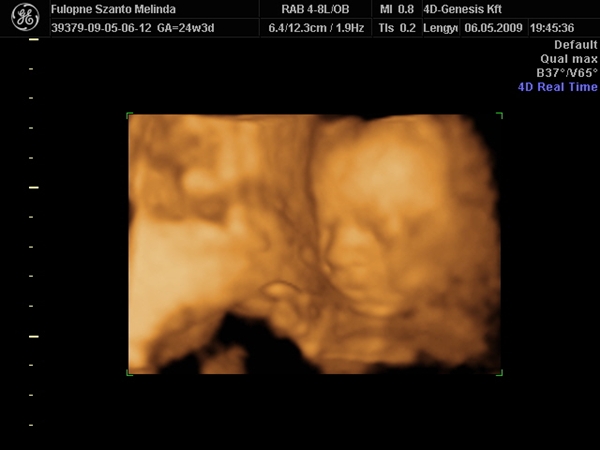

Na rakok képet,Budán voltunk a 4d genesis,de megmutatom,van honlapja.... Kép Kép Kép Kép Kép

Szóval!Nagyon csodálatos volt látni (nekem újra) a picúrt! :lol:

Mint ahogy kiderült,nem is olyan picúr!Ma vagyok 15 hét 2 napos,a bab méretei meg 16 hetesnek felel meg.Persze tudom,ez még változhat.Szegénykém olyan furi pózt vett fel,de hát ha neki úgy kényelmes,legyen úgy! :lol: :lol: :lol: :wink: Úgy képzeljétek el,mint a fordított C betű.Lent van a feje,felfelé áll a törzse és balra fordulva a lábai.Nem tudom elég érthető volt e így,de sajna jobban nem tudom elmagyarázni.

Ja, igen a 27.hét környékén, már nagyon kis formásak, van rajtuk husi és a vonások is jól látszanak! Meg a végén, nagyon jó a kis arcuk!

Nekem van olyan, ami szülés előtt 3 nappal készült és Pepe vonásai annyira felismerhetőek, hogy nagyon! Nagyon érdekes dolog ez!